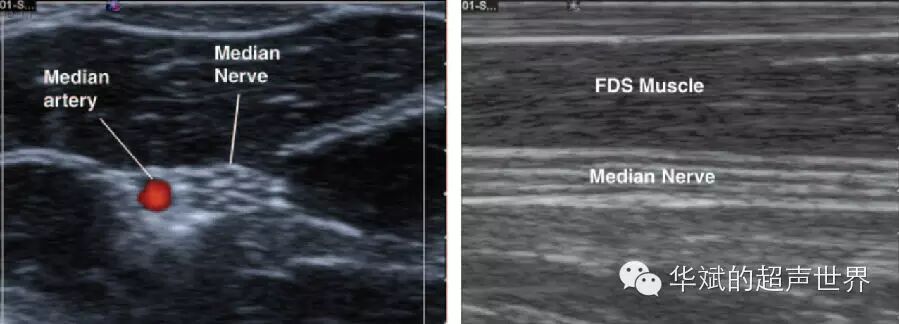

外周神经一般位于筋膜间隙内,高频超声下的神经在短轴上显示为筛网状结构(图1),强回声代表神经束膜,低回声代表神经束本身。长轴扫查,神经显示为平行的索条样强回声,与肌腱回声类似。

1 前臂正中神经。左图为横断,神经微筛网状结构;右图为纵断,神经显示为平行的索条样强回声。Median Nerve:正中神经,FDS Muscle:指浅屈肌,Median artery:正中动脉